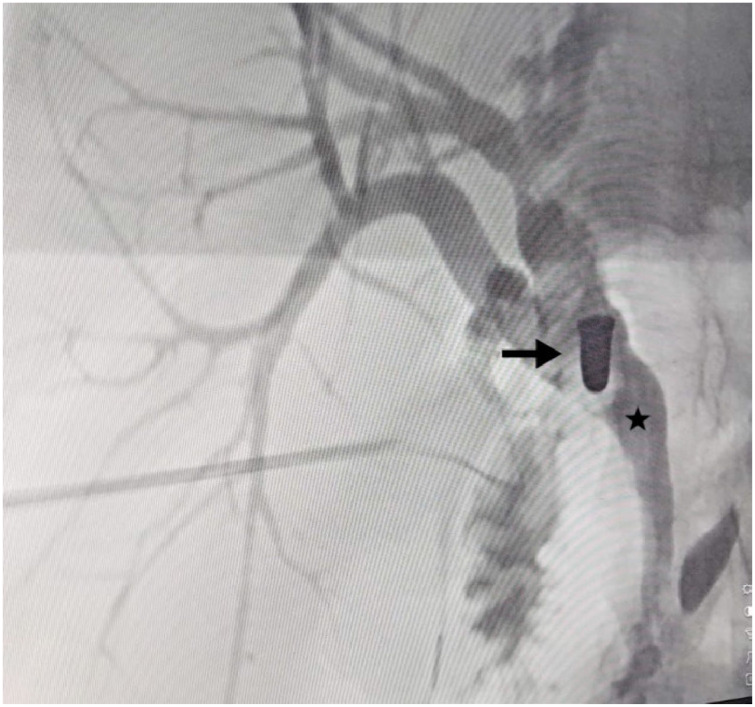

Case presentation: A 41-year-old female with a 13-year history of an accidental gunshot wound, which required an emergency laparotomy, presented to our hospital with symptoms of cholangitis. Endoscopic retrograde cholangiopancreatography was performed, revealing a bullet that caused significant dilation of the proximal bile duct. Exploratory laparoscopy, cholecystectomy, and intraoperative cholangiography confirmed the presence of the bullet. The procedure included a choledochotomy and removal of the bullet, followed by primary closure of the common bile duct using interrupted 4-0 Prolene sutures. The patient was discharged on the 11th postoperative day, and follow-up revealed complete resolution of symptoms and normal liver function.